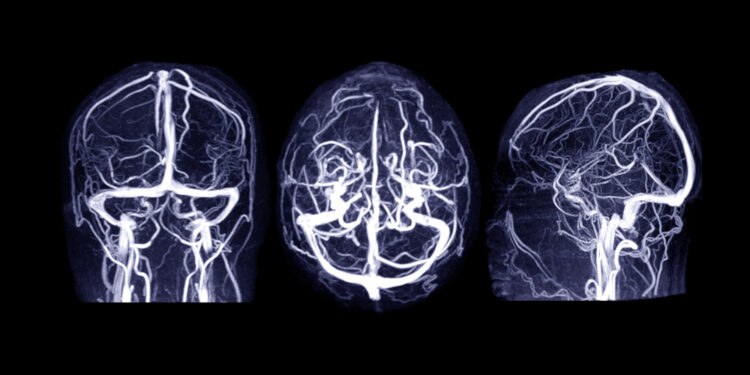

Norint patikimai nustatyti galvos veninių ančiu trombozę, būtina atlikti smegenų tyrimus vaizdinimo metodais.

Pagrindiniai diagnostiniai tyrimai:

- Smegenų magnetinio rezonanso tomografija (MRT) su kontrastu

- Kompiuterinė smegenų tomografija (KT) su kontrastu

- Venografija (MRV arba KT venografija), smegenų angiografija

Praėjus trims–šešiems mėnesiams po trombozės, gydytojai dažnai rekomenduoja atlikti pakartotinius smegenų kraujotakos tyrimus (CT ar MRT su kontrastu), kad įvertintų gydymo sėkmę ir kraujagyslių būklę.